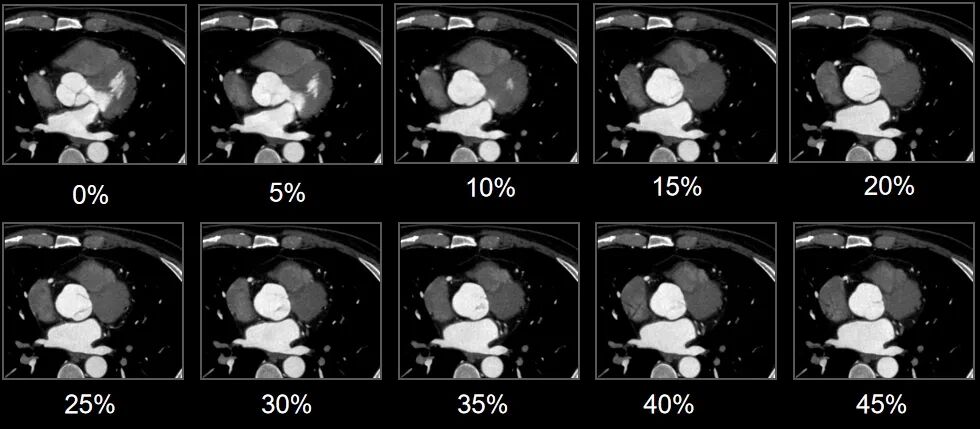

一直以来,冠脉CTA扫描对患者心律和扫描条件要求较高,传统单源宽体系统受限于时间分辨率,往往在心脏收缩末期或舒张中期获得可用于临床诊断的冠脉CTA图像。

令人欣喜的是,uCT SiriuX凭借8ms超高时间分辨率和全心覆盖,可以做到在单心动周期内的任意时相获取高质量的冠脉CTA图像

我们来看成像效果!

单心动周期全心全时相高清成像图